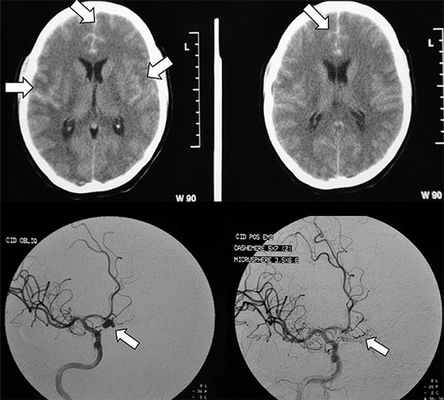

Рисунок 2. Как выглядит субарахноидальное кровоизлияние на диагностическом снимке. Источник:Brazilian Journal of Psychiatry (Creative Commons Attribution Non-Commercial License)

В классификации Фишера вид кровоизлияния оценивается по данным компьютерной томографии, в ней выделяется четыре группы:

- I группа – КТ не показывает наличие кровив субарахноидальном пространстве,

- II – диффузное кровоизлияние или сгустки крови в субарахноидальном пространстве толщиной до 1 мм,

- III – сгустки крови в субарахноидальном пространстве толщиной более 1 мм,

- IV – сгустки крови в субарахноидальном пространстве в сочетании с внутрижелудочковым или внутримозговым кровоизлиянием.

- Компьютерная томография помогает определить стадию САК, его выраженность и выявить наличие крови в желудочках мозга или веществе мозга.

Компьютерная томография

Чувствительность КТ к наличию крови в субарахноидальных пространствах связанна с количеством крови и временем, прошедшим с момента кровоизлияния.

Диагноз подозревается при наличии высокоплотного прокрашивания субарахноидальных пространств.

В большинстве случаев наблюдается около Виллизиевого круга, поскольку большинство мешотчатых аневризм локализуется в этой области (~65%), или в Сильвиевой щели (~30%) ref needed. Небольшие по количеству крови кровоизлияния могут иногда быть выявлены за счет скопления в медножковой цистерне или в виде гиперденсивного треугольника в затылочном роге бокового желудочка [5]. Субарахноидальные кровоизлияния разделяют на 4 категории в соответствии со шкалой Фишера, в зависимости от количества крови.Магнитно-резонансная томография